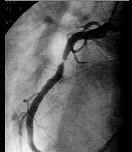

问题 图中冠状动脉造影结果为 ( )

选项 A、右冠近端95%狭窄 B、左冠前降支近端95%狭窄 C、右冠远端95%狭窄 D、左冠回旋支95%狭窄 E、左主干近端95%狭窄

答案 A